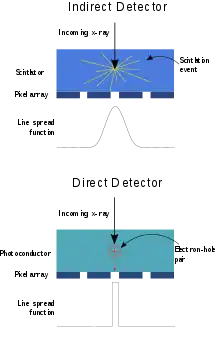

Indirect detectors contain a layer of scintillator material, typically either gadolinium oxysulfide or cesium iodide, which converts the x-rays into light. Directly behind the scintillator layer is an amorphous silicon detector array manufactured using a process very similar to that used to make LCD televisions and computer monitors. Like a TFT-LCD display, millions of roughly 0.2 mm pixels each containing a thin-film transistor form a grid patterned in amorphous silicon on the glass substrate.[1] Unlike an LCD, but similar to a digital camera's image sensor chip, each pixel also contains a photodiode which generates an electrical signal in proportion to the light produced by the portion of scintillator layer in front of the pixel. The signals from the photodiodes are amplified and encoded by additional electronics positioned at the edges or behind the sensor array in order to produce an accurate and sensitive digital representation of the x-ray image.[2]

Direct conversion imagers utilize photoconductors, such as amorphous selenium (a-Se), to capture and convert incident x-ray photons directly into electric charge.[3] X-ray photons incident upon a layer of a-Se generate electron-hole pairs via the internal photoelectric effect. A bias voltage applied to the depth of the selenium layer draw the electrons and holes to corresponding electrodes; the generated current is thus proportional to the intensity of the irradiation. Signal is then read out using underlying readout electronics, typically by a thin-film transistor (TFT) array.[4][5]

By eliminating the optical conversion step inherent to indirect conversion detectors, lateral spread of optical photons is eliminated, thus reducing blur in the resulting signal profile in direct conversion detectors. Coupled with the small pixel sizes achievable with TFT technology, a-Se direct conversion detectors can thus provide high spatial resolution. This high spatial resolution, coupled with a-Se's relative high quantum detection efficiency for low energy photons (< 30 keV), motivate the use of this detector configuration for mammography, in which high resolution is desirable to identify microcalcifications.[6]